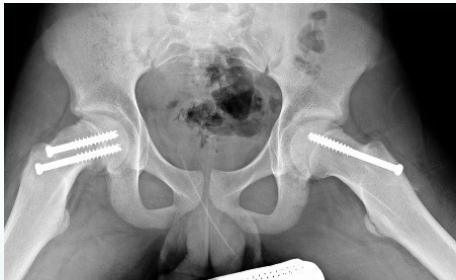

Treatment:

- Conservative:

- Rest

- Physiotherapy: abduction and rotation exercises

- Containment using abduction splint

- Surgical:

- Containment procedures: To improve femoral head coverage

- Acetabuloplasty

- Femoral varus osteotomy

- Late procedures: For residual deformity or problems